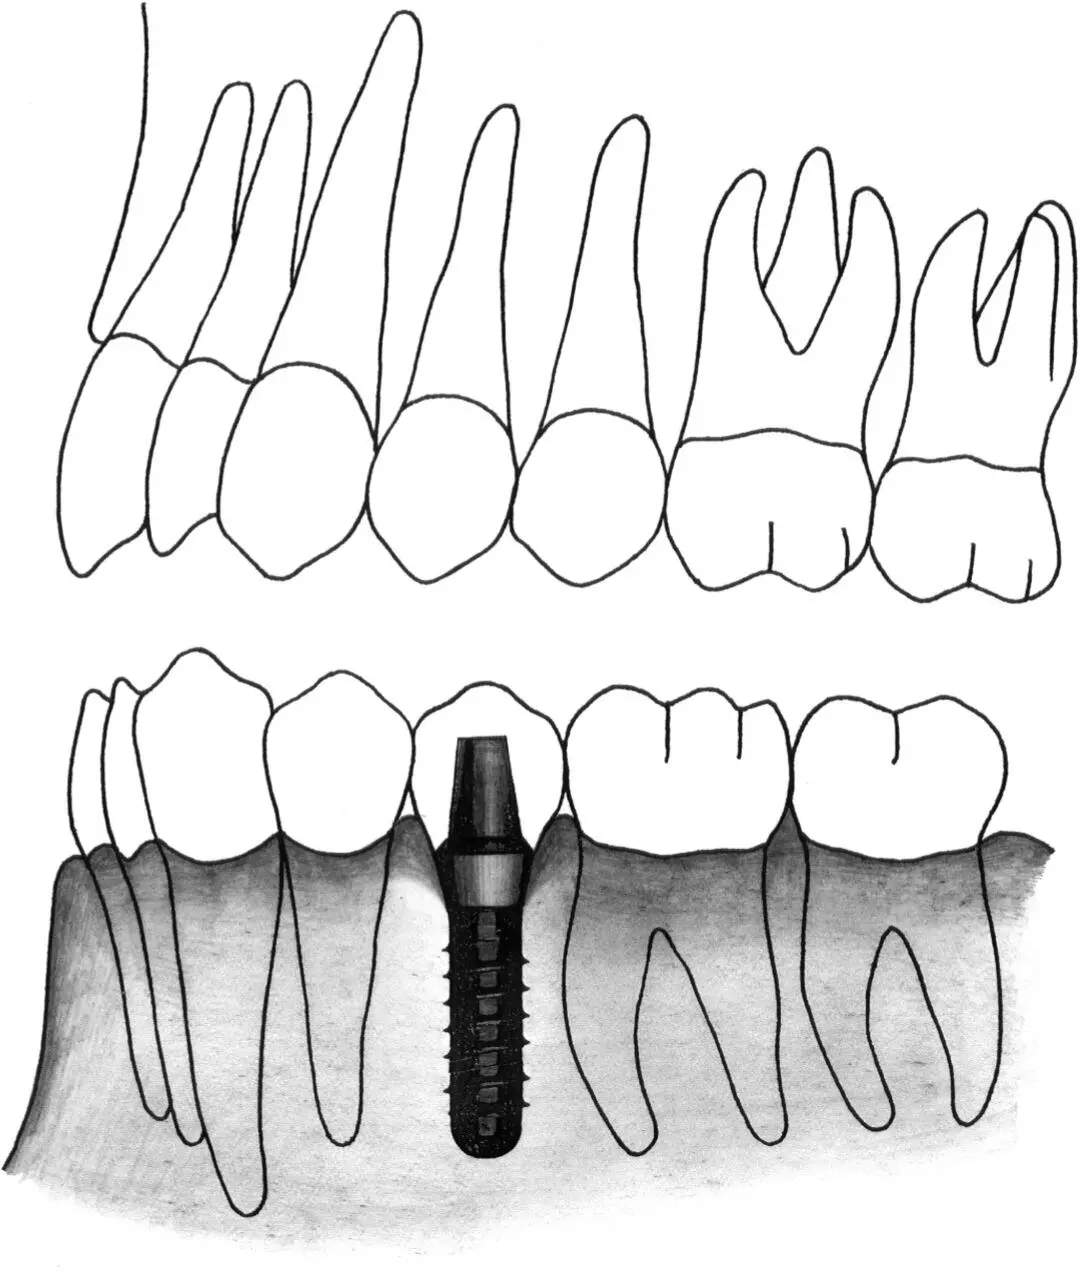

Figs 1-11i and 1-11j Occlusal (i) and lateral (j) views of implants positioned in the first premolar and first molar sites. In this extended posterior distal extension situation, a regular neck implant and a wide neck implant are indicated as abutments for a three-unit fixed partial denture. The regular neck implant is positioned 4 to 5 mm from the tooth. The wide neck implant is inserted about 16 mm from the anterior implant.